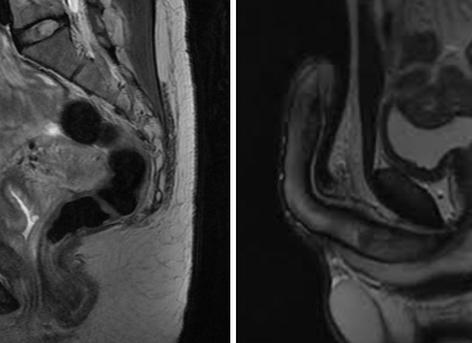

МРТ малого таза. Эндометриоз матки. Матка увеличена в размерах и соответствует 7-8 неделям беременности (но пациентка не беременна, просто такая большая матка в следствие эндометриоза). Множественные включения указано стрелкой.

Клиническая картина зависит от локализации патологического образования, но общими признаками являются болевой синдром, нарушение менструального цикла, бесплодие. В связи с различными вариантами расположения очага, МРТ является основным неинвазивным методом диагностики. На Т1-взвешенных изображениях эндометриоз выглядит как очаг высокой интенсивности с четкими контурами за счет фиброзной капсулы, которая образуется вокруг образования любых размеров. Для Т2-томограмм характерен симптом затенения, очаг имеет низкую интенсивность окрашивания.

Аденомиоз. Эндометриоидная киста слева. Наружные эндометриоидные гетеротопии слева (аксиальные срезы. Т2-взвешенное изображение и Т1-взвешенное изображение).